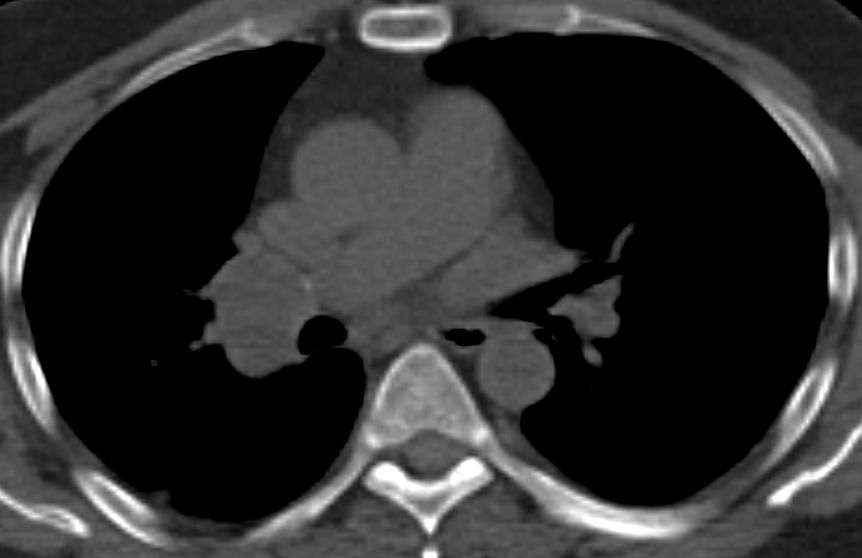

blauer Punkt 65mm großes Adenokarzinom des rechten Lungenoberlappens mit Infiltration der dorsalen Thoraxwand.